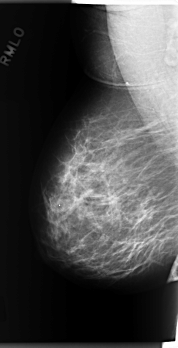

C_0277_1.LEFT_MLO

RIGHT_MLO LINES 5904 PIXELS_PER_LINE 3024 BITS_PER_PIXEL 12 RESOLUTION 50 NON_OVERLAY